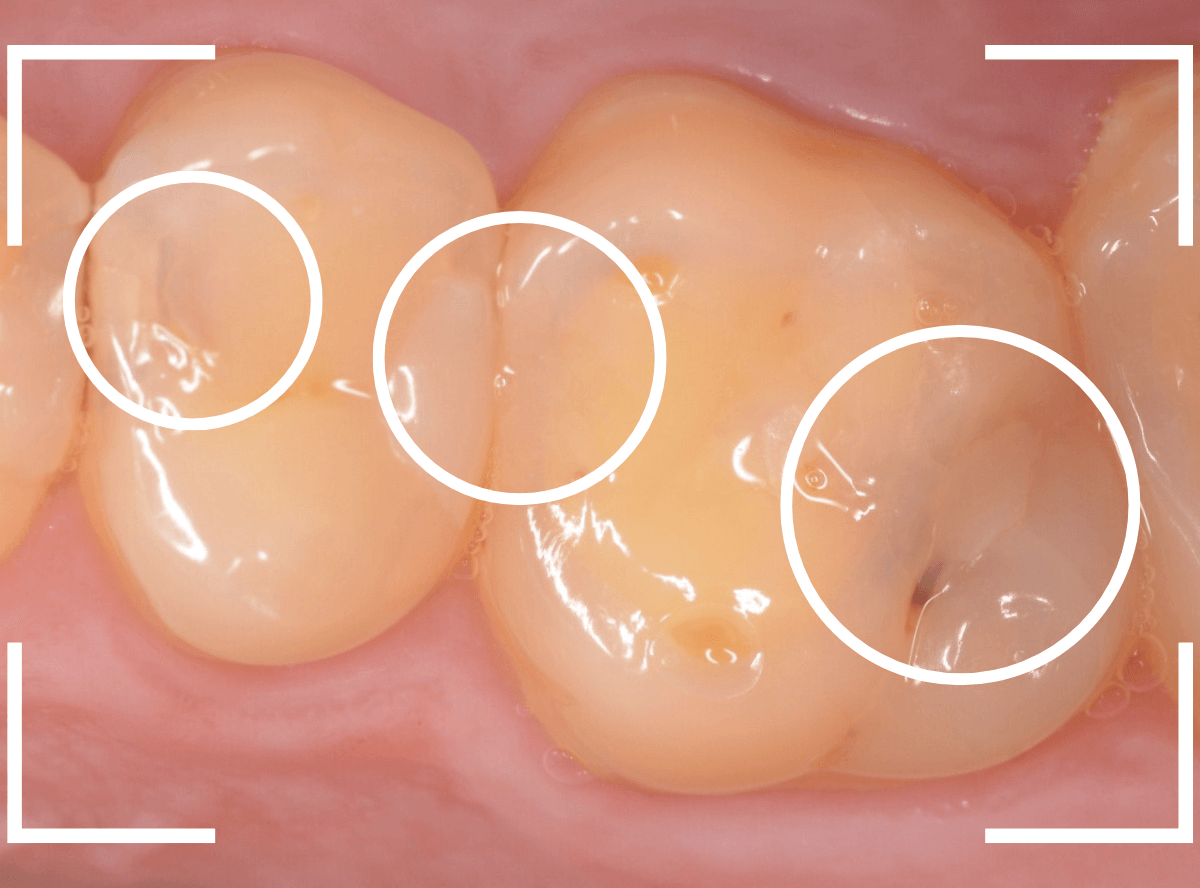

Case.29

舌のそばの虫歯とセラミック治療

下の奥歯が虫歯になった患者さんのケースです。

〇部が虫歯の部分です。

写真で見てわかるように、常に舌が歯に触っているような状況です。

このような場合、虫歯を見つけづらいですし、治療の難易度もあがります。